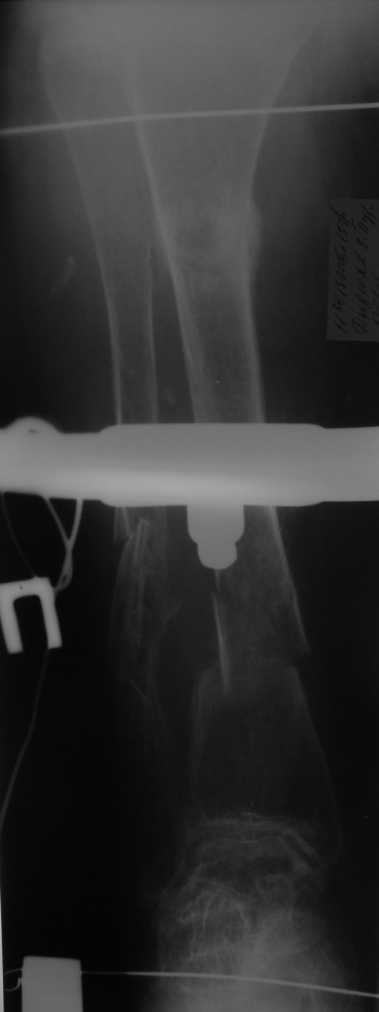

Уважаемые коллеги! Здравствуйте! Прошу у Вас совета вот по какому случаю.В нашу клинику поступила женщина 71 год. Травма в результате ДТП. (Пациентка передвигалась на инвалидной каляске и была сбита автомобилем). Диагноз: Множественная травма. Перелом нижней трети правого бедра. Перелом средней трети правой б/берцовой, малоберцовой кости, нижней трети левой большоберцовой, м/берцовой кости.Травматический шок. Со стороны внутренних органов и систем без патологии. Больная госпитализирована в реанимационное отделение, где было наложено двойное скелетное вытяжение за правую н/конечность. Левая н/конечность иммобилизована гипсовой лонгетой. Из анамнеза: больная является инвалидом 1 группы по опорно-двигательному аппарату. В детстве перенесла рахит. Осложнением которого "О" образная деформация нижних конечностей. Ограничено отведение нижних конечностей, деформирующий артроз тазобедренных и коленных суставов. В 1990 году перелом правого бедра остеосинтез пластиной. После операции больная передвигалась только на костылях или в инвалидной коляске.

Прошу прощения за качество снимков. Р-графия производилась в реанимационном отделении передвижным аппаратом.

Но даже при малоинвазивной методике лечения применимой для даной больной существуют следующие проблемы: выраженный остеопороз, тонкий кортикал, очень широкий канал.

Проблема в том, что в сагитальной плоскости угол голеней =30 градусам. Ширина канала 30.